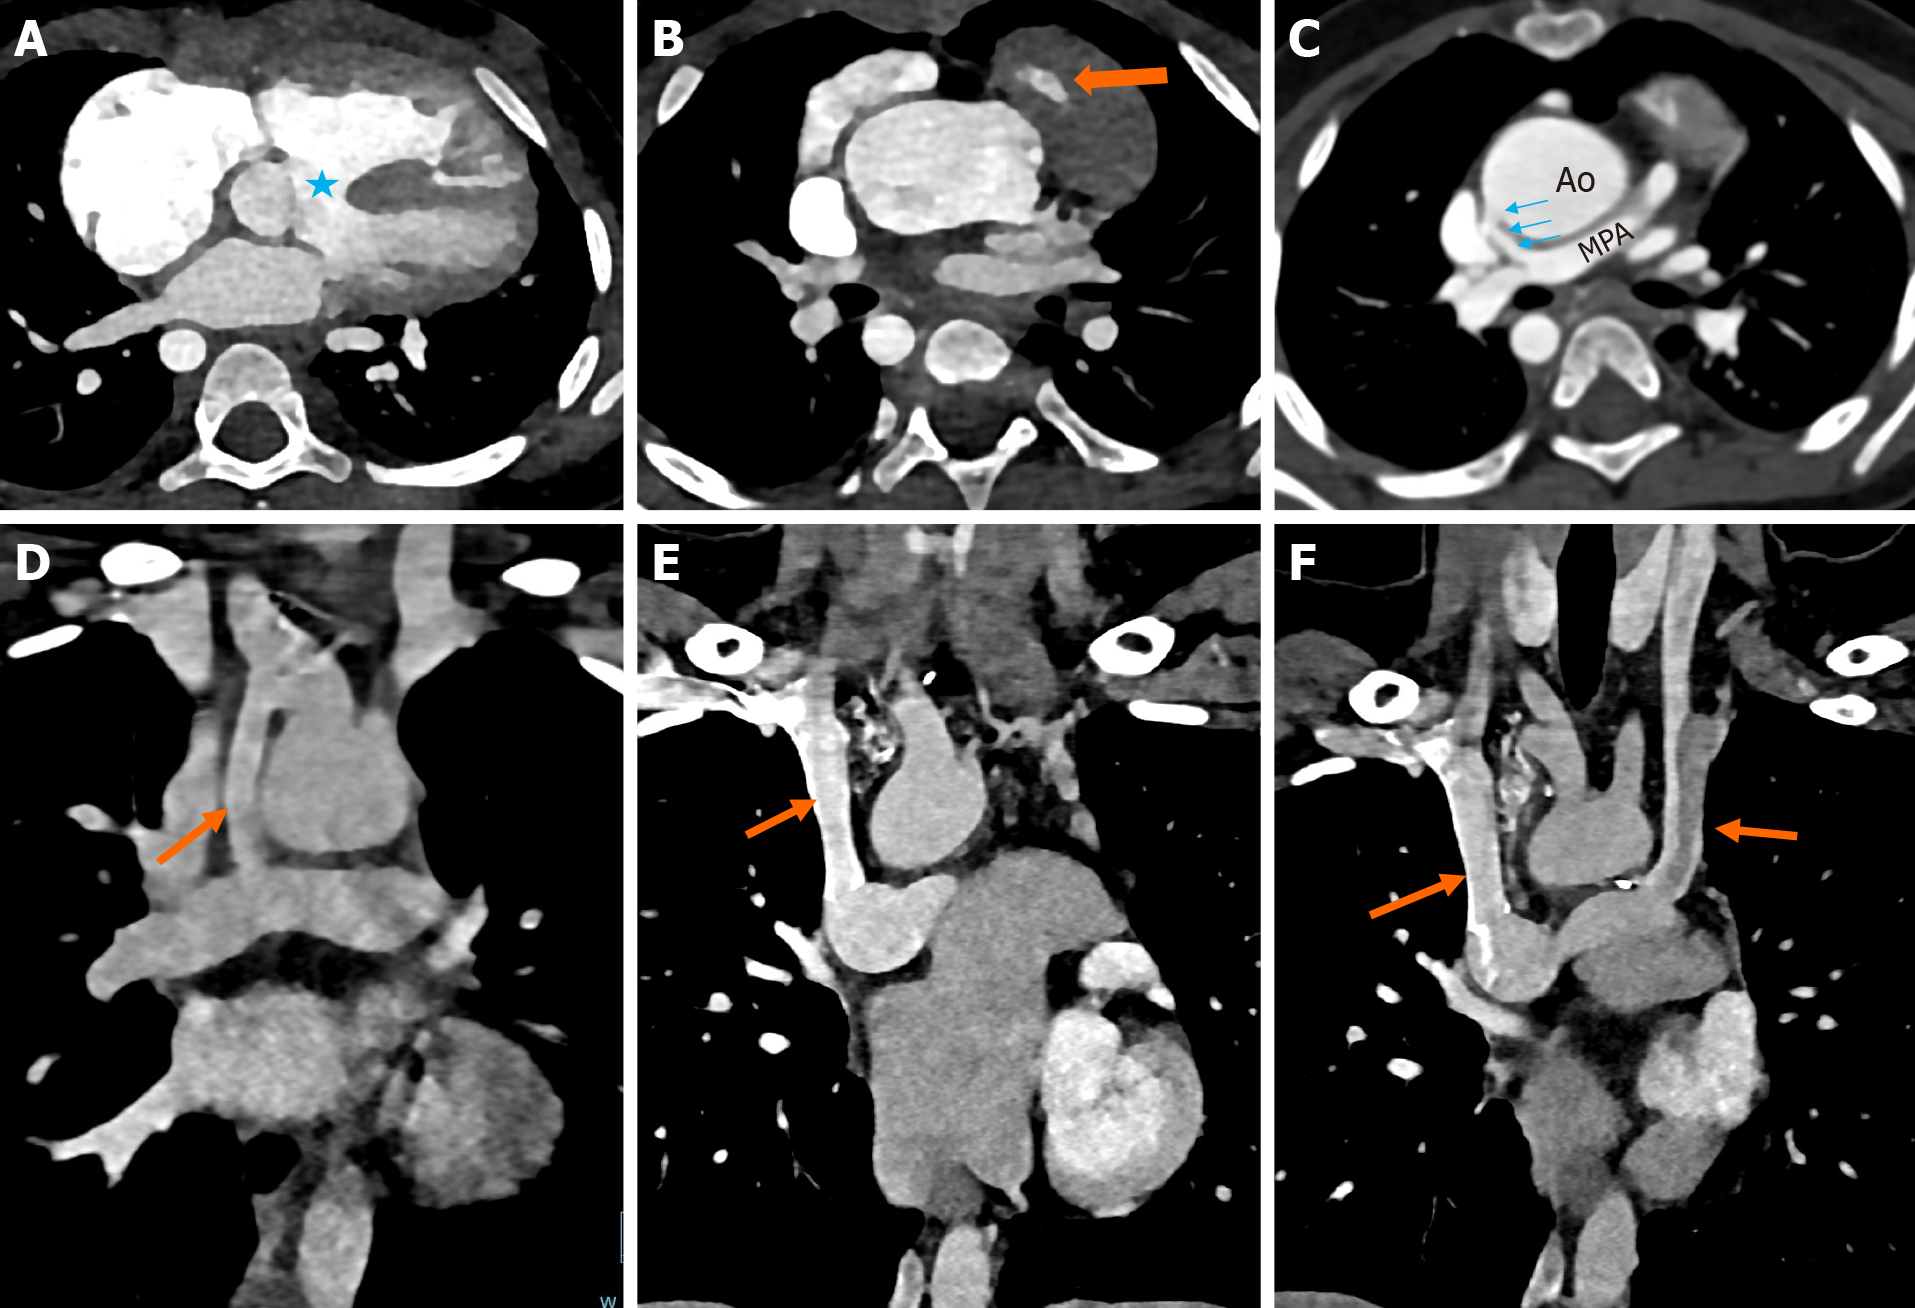

Figure 6 Computed tomography images. A-D: Oblique axial maximum intensity projection images and volume rendered image showing supravalvular main pulmonary artery (orange arrow) and right pulmonary artery (blue arrow) stenosis in a known case of TOF (A); coronal reformat image showing the main pulmonary artery stenosis (arrow) (B); coronal reformat image showing right pulmonary artery stenosis (blue arrow) (C); three-dimensional volume rendered image showing supravalvular main pulmonary artery stenosis (arrow) (D); E-H: Axial computed tomography angiography images showing pulmonary arterial anomalies in different patients of tetralogy of Fallot. E: Pulmonary atresia (block arrow) with reformed, confluent pulmonary arteries (asterisk); F: Pulmonary atresia with non-confluent, reformed pulmonary arteries (block arrow); G: Pulmonary atresia with absent main and branch pulmonary arteries (block arrow); H: Aneurysmal dilatation of the main pulmonary artery (block arrow) due to absent pulmonary valve.

In pulmonary atresia and severe pulmonary stenosis, the pulmonary circulation is maintained by a patent ductus arteriosus (PDA) and/or aortopulmonary collaterals. PDA shunts blood from the aorta to either of the pulmonary arteries (Figure 7A and B). Major aortopulmonary collateral arteries (MAPCAs) are larger than 3 mm in caliber, by definition. MAPCAs generally develop from the descending thoracic aorta and its branches (Figures 7C-F and 8A-C). Rare sources of MAPCAs include the celiac trunk and the coronary arteries[39]. When present, the origin and course of MAPCAs are to be clearly mentioned in the report, including the corresponding vertebral level, origin by clock position, and laterality[40]. While perimembranous VSD is characteristically present in TOF, other types of VSDs may be co-existent, including muscular VSD and doubly committed subarterial VSD, with or without perimembranous extension[41]. Although two-dimensional echocardiography is more sensitive than CT for the detection of ASDs, larger ASDs can be confidently identified on CT (Figure 8D and E).

Figure 7

Figure 7 Computed tomography images. A and B: Axial (A) and volume rendered image (B) of computed tomography angiography in a child with tetralogy of Fallot showing a large patent ductus arteriosus between the descending thoracic aorta and left pulmonary artery; C-F: Axial (C and D) and coronal reformatted images (E and F) of computed tomography angiography in a child with tetralogy of Fallot showing major aortopulmonary collateral arteries in the mediastinum arising from the descending thoracic aorta (block arrows) and reforming the right and left pulmonary arteries.

Figure 8

Figure 8 Computed tomography images. A-C: Axial (A and B) and coronal reformatted images (C) of computed tomography angiography in a child with tetralogy of Fallot showing systemic aortopulmonary collateral artery in the right paratracheal location arising from the right subclavian artery and reforming the right pulmonary artery; D and E: Axial image of computed tomography angiography showing a large atrial septal defect in a patient with tetralogy of Fallot consistent with pentalogy (D); Sagittal reformat of another patient showing a small muscular ventricular septal defect (block arrow) in addition to the perimembranous ventricular septal defect (E).